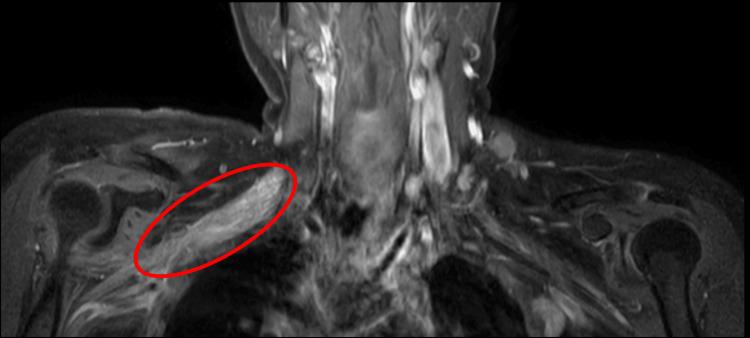

This report illustrates the case of a 37-year-old woman following chemoradiotherapy for invasive ductal carcinoma of the right breast. The patient underwent surgery and received a radiation dose of 50 gray to the chest wall and 45 gray to the regional lymph nodes in 25 total fractions. She developed motor and sensory weakness in the right upper limb eight years after treatment. Brachial plexus neuropathy in cancer patients may result from either trauma to the plexus during surgery, the spread of cancer, or radiation therapy, and distinguishing between them may be difficult. The case highlights the importance of recognizing the signs, symptoms, and possible differential diagnosis of radiation-induced brachial plexopathy in cancer patients post-radiation therapy. It emphasizes the role of magnetic resonance imaging in the careful assessment and diagnosis of such a case.

本报告阐述了一名37岁女性在接受右乳浸润性导管癌放化疗后的病例。该患者接受了手术治疗,并在25次分次放疗中,胸壁接受了50格雷的辐射剂量,区域淋巴结接受了45格雷的辐射剂量。治疗八年后,她出现了右上肢运动和感觉无力的症状。癌症患者的臂丛神经病变可能是由于手术过程中对神经丛的创伤、癌症扩散或放射治疗引起的,区分它们可能很困难。该病例强调了识别癌症患者放疗后放射性臂丛神经病变的体征、症状及可能的鉴别诊断的重要性。它强调了磁共振成像在仔细评估和诊断此类病例中的作用。